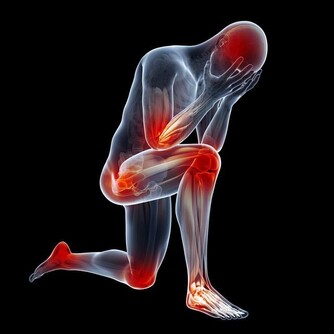

- 脊椎與關節疼痛:錯誤的睡姿會造成頸椎、腰椎與肩膀疼痛,影響長期健康。